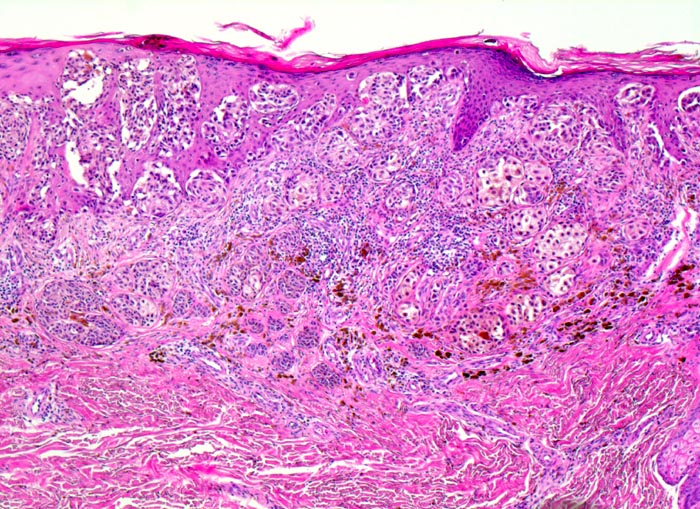

oberflächlich spreitendes Melanom (SSM)

maligner Tumor

Haut, untere Extremität

Asymmetrischer melanozytärer Tumor bestehend aus auffallend grossen Zellnestern, welche zur Tiefe hin kaum an Grösse abnehmen und sich auch in oberen Anteilen der Epidermis ausbreiten.

Leicht erhabener scharf begrenzter brauner in der Mitte dunkelbraun gefärbter Bezirk, max. Dm 15mm Infiltration des Stratum papillare bis an das Stratum reticulare und einer max. Tumordicke von 1,12mm (pT2; Clark Level III).

Verdächtiger Nävus Kniekehle links.